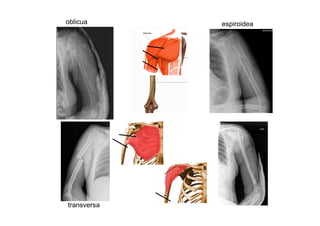

4.1 . Fracturas diafisarias de

húmero:

• 3% de todas las fracturas.

• Dos picos de edad:

– Jóvenes por traumas de alta E.

– Mujeres >70 años osteoporóticas.

• Aparece parálisis radial (casi

siempre transitoria) en el 18% de

las fracturas cerradas.

• Fractura de Holstein Lewis

(Fractura espiroidea de tercio

distal con desplazamiento radial

de fragmento proximal)

oblicua espiroidea

transversa